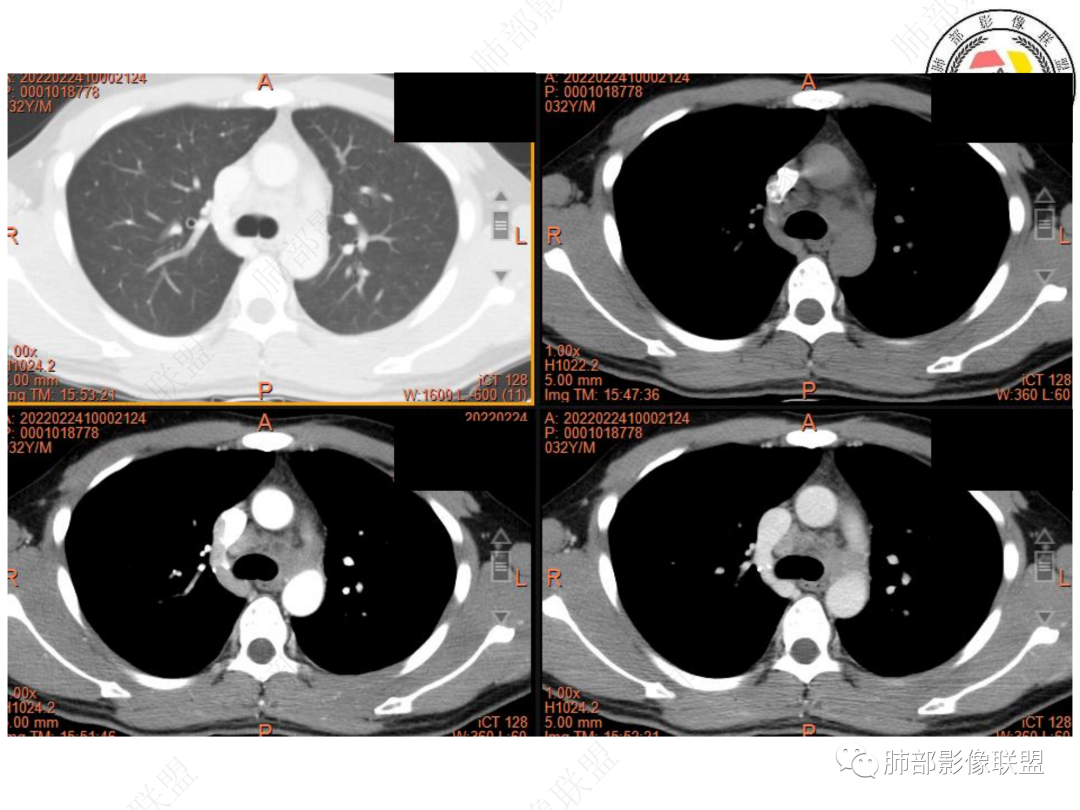

1. 青年男性,偶然发现左肺下叶结节影,左肺门及纵隔内多发淋巴结肿大,并坏死。

3. CT示左肺下叶背段孤立实性密度结节影,边缘比较清楚光滑,总体呈现膨隆感,未见分叶毛刺,少张力,部分层面病灶边缘呈现较清楚磨玻璃样密度影,并于磨玻璃影病灶内可见多发小空泡,未见钙化或空洞,增强后病灶显示不均匀强化,未见低密度液化区。未见卫星病灶。

左肺门及纵隔内多发淋巴结肿大,大部分淋巴结显示融合,强化不均匀,内见低密度区,疑液化坏死。纵隔内淋巴结部分周围脂肪间隙不清晰。大血管及左肺主支气管未见受侵改变。